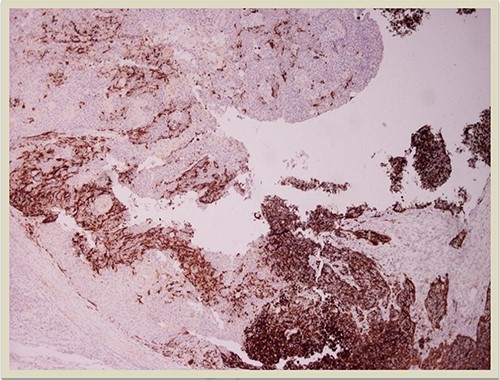

HMB45 × 4: HMB45 immunostain highlights the malignant melanocytic component ( ×10 magnification).